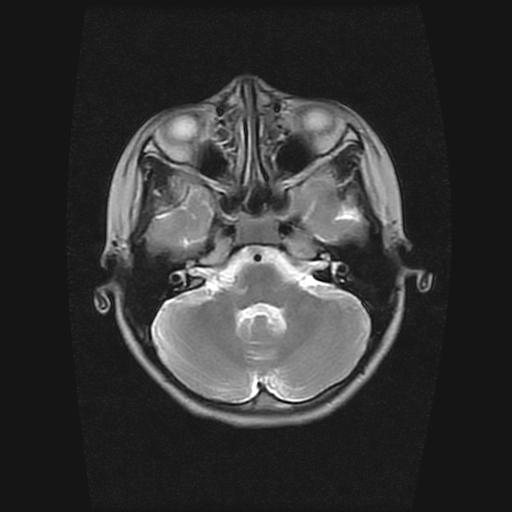

9岁女孩,三岁时诊断为癫痫,一直服丙戊酸钠,现患者一般情况良好,家长复查核磁片,看能否停药..

巨脑回